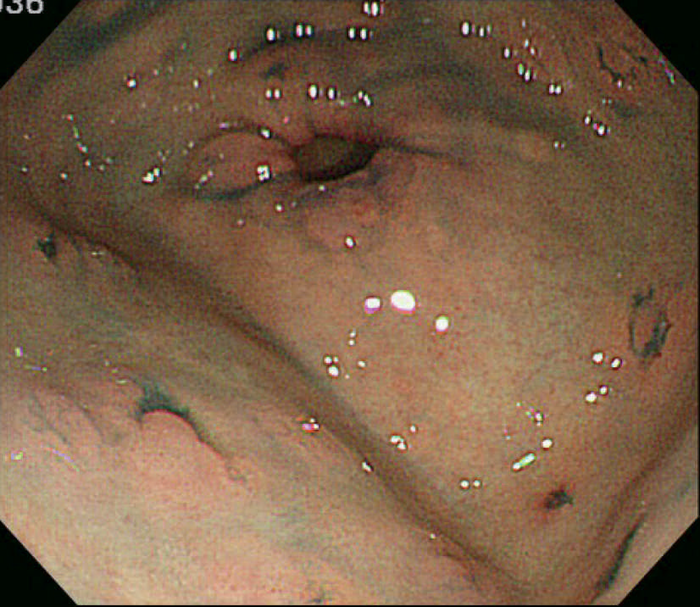

- 胃底腺ポリポーシス(図Ⅱ-6)は健常人にみられる胃底腺ポリープとは数や大きさが異なり特徴的で,FAP症例の88%にみられ73),補助診断として参考になる。

- 胃底腺ポリポーシスの中に腺腫(図Ⅱ-7),および癌が発生しうる。

図Ⅱ-6 胃底腺ポリポーシス